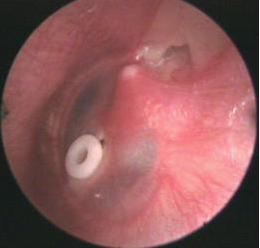

西安新城中大耳鼻喉医院医生表示:用耳内窥镜检查病人的耳部,会发现鼓膜内陷,鼓膜呈淡黄或橙红色,有时透过鼓膜可见气泡。

(3)鼓室置管术: 长期不愈或反复发作者,鼓室积液清除后,可经鼓膜留置通气管于鼓室内,以改善通气引流,有利于恢复咽鼓管功能。详细治疗方案可拨打免费医生电话029-87401000

中耳炎鼓室置管

通气管留置时间一般为6—8周,长可达半年至一年。待咽鼓管功能恢复后,通气管常自行排出于外耳道内。另外,紫外线或超短波,激光照射等物理疗法,可改善中耳血液循环,促进积液吸收。